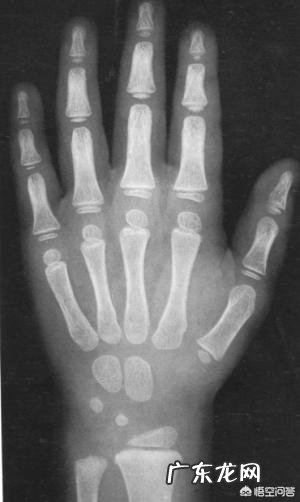

骨龄检查,即手掌X射线检查,查看骨骺线闭合程度等;

经检查,骨龄落后于实际年龄;